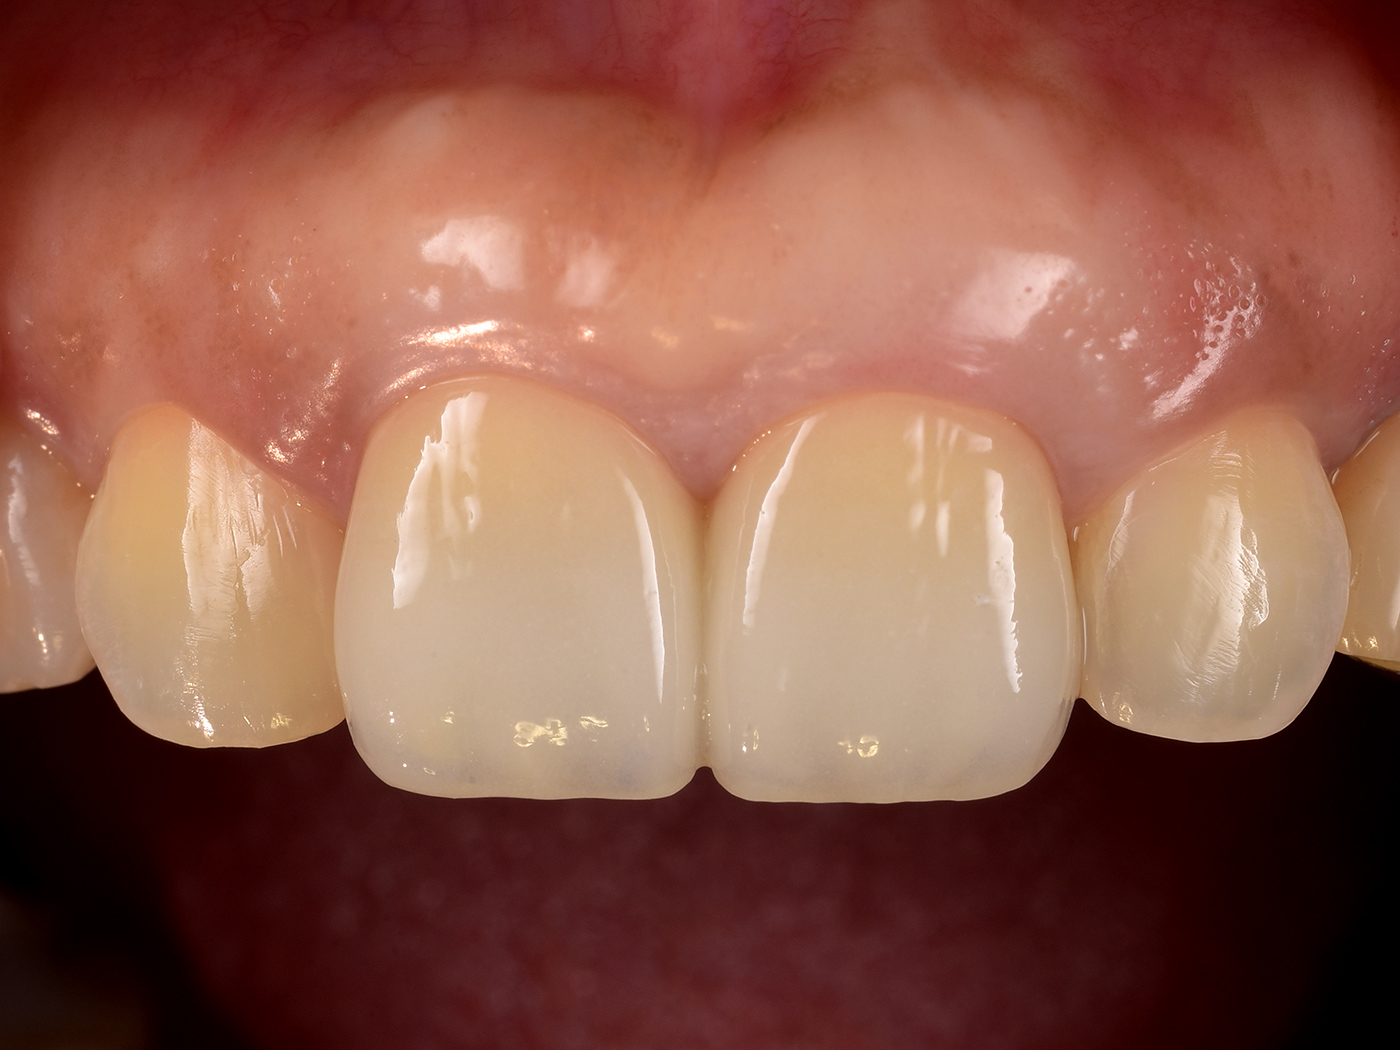

治療後4年経過

長期安定を確認

重度の歯根破折からの回復後、無事4年が経過しました。

患者さんからは、「抜歯しかないと諦めていた歯が残せただけでなく、見た目も自然で美しく、固いものでも気にせず食べられるようになった」と大変ご満足いただいております。今後も引き続き、患者さんと共に注意深く経過を観察してまいります。